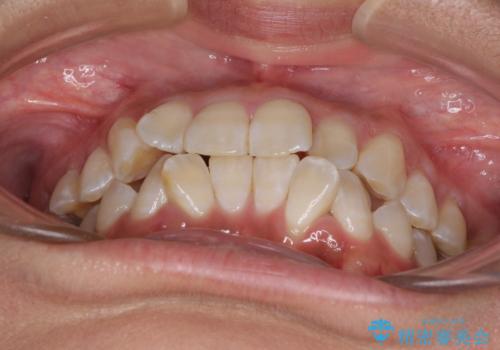

- 以前矯正治療を行ったものの、思い通りの仕上がりではなく、更には後戻りが気になってきたとのことで来院された患者様です。

上顎右側の第一小臼歯が動きにくい歯であり、以前矯正治療を行った際に傾斜した位置のまま終了したことと、それに伴い後戻りで歯列が波打っているようになっていることを大変気にしていらっしゃいました。

咬合平面改善のため、アンカースクリューを多用し、ワイヤー装置にて矯正治療を行うこととしました。

動きにくい歯はやはり動きにくく、咬み合わせ改善に時間を要しましたが、患者様には大変満足していただけました。